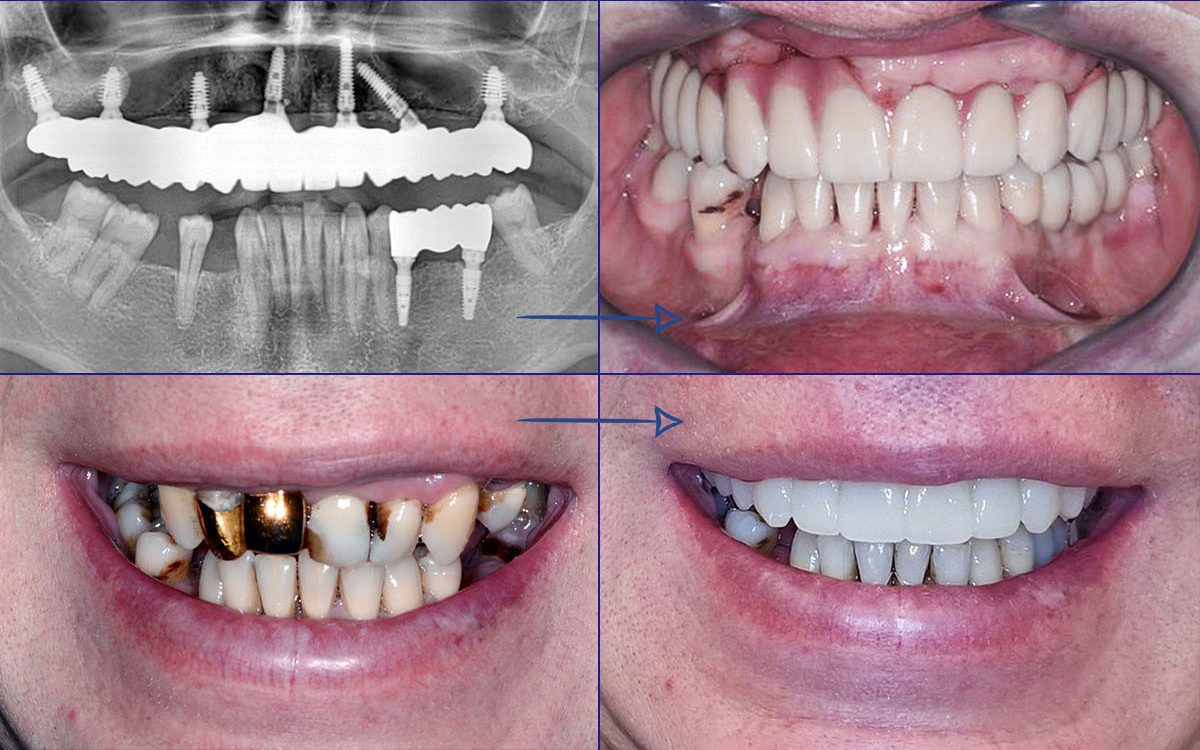

„All-on-4“ yra pažangi dantų implantavimo technika, leidžianti atkurti visą viršutinio arba apatinio žandikaulio dantų lanką vos su 4 implantais. Ant šių implantų fiksuojamas nuolatinis dantų protezas, kuris užtikrina ne tik estetišką šypseną, bet ir pilnavertę kramtymo funkciją. Šis metodas yra greitas, komfortiškas ir daugelio specialistų pripažįstamas kaip vienas efektyviausių sprendimų bedančiams žandikauliams netekus daugelio ar visų dantų.

- Dantų protezai ant 4 implantų vos per 24 – 48 val. Ir turite naujus visus dantis!